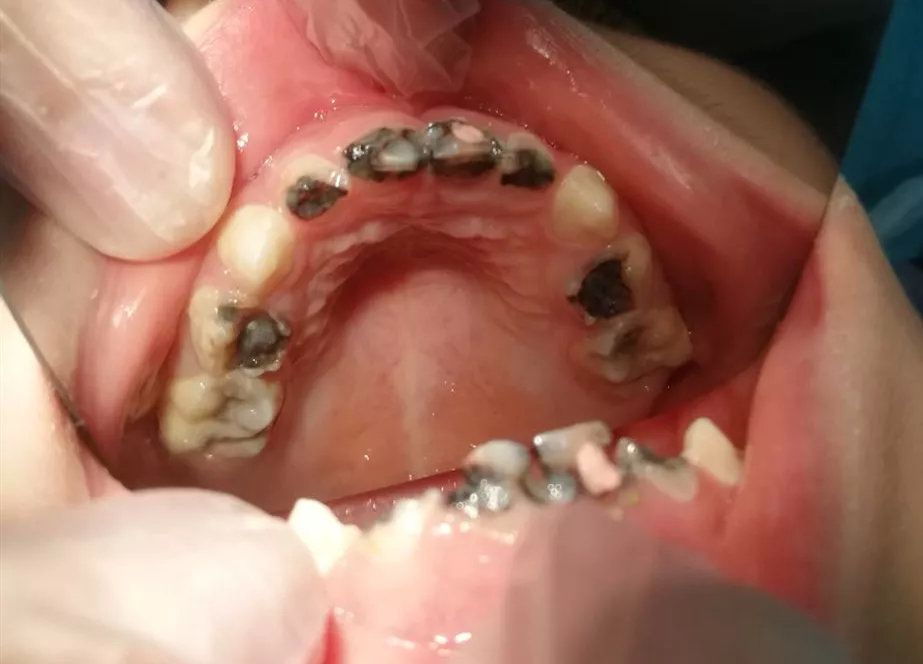

Lỗ sâu răng vào tủy là tình trạng sâu răng tiến triển nặng, vi khuẩn đã phá hủy lớp men răng và ngà răng, xâm nhập vào tủy răng – nơi chứa các dây thần kinh và mạch máu. Khi đó, người bệnh thường cảm thấy đau nhức dữ dội, ê buốt kéo dài, đặc biệt khi ăn uống nóng, lạnh hoặc ngọt. Nếu không điều trị kịp thời, vi khuẩn có thể gây viêm tủy, áp xe răng và thậm chí mất răng.

✔ Có lỗ sâu lớn, đen, đôi khi nhìn thấy phần tủy răng bị tổn thương